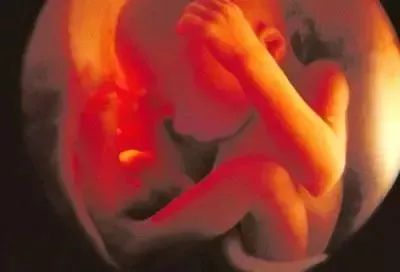

五个月:艰难和幸福的诞生已经过去了一半。婴儿头上有长发,眉毛和睫毛长出来,身体的绒毛状长度覆盖整个身体;长度20~30厘米,体重250~300克;子宫内位置合适;如果耳朵靠近母亲的腹部,你可以听到他。胎儿的节拍;此时,有一层油腻的白色物质覆盖在心脏上。这种物质覆盖胎儿全身,被称为胎儿皮脂,它长期保护羊水中胎儿皮肤,并在生产过程中减少婴儿通过产道的阻力。

六个月:身高23-34厘米,体重660克。身体逐渐匀称。皮下脂肪不是很累进,所以它又瘦又黄。从这一点开始,皮肤脂肪附着在皮肤表面。胎儿脂肪是皮脂腺分泌的皮脂和脱落的皮肤上皮的混合物。他的身体在和谐中生长,很快就会增加脂肪;他的眼睛是完全的,睁开的,闭着的,四处张望,呼吸正常,哭泣,手可以紧握;他的身体在生长,更多的脂肪很快就会增加。